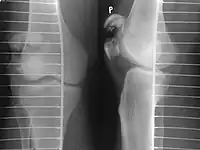

A vertical patella fracture with the fracture line marked by a black arrow

Diagnosis is based on symptoms and confirmed with X-rays.[3] In children an MRI may be required.[3]